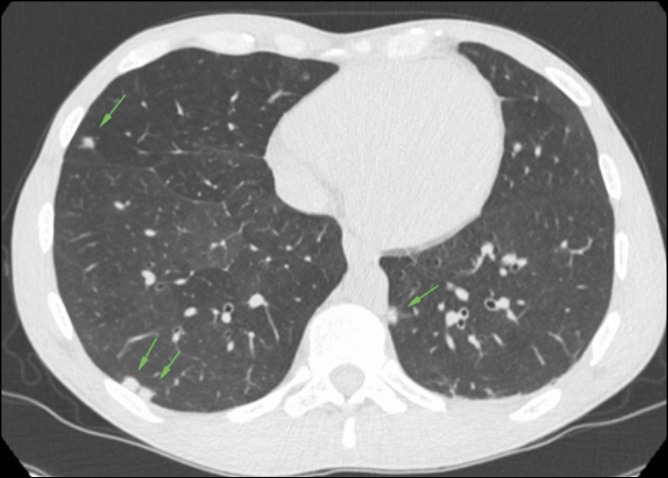

A 31-year-old man who have sex with man (MSM), living with HIV and with mild dyslipidemia went to our Emergency Room (ER). Two months earlier he performed a routinary blood test in our outpatients clinic, which showed a good immune-virological status: HIV-RNA not detected, CD4+ count 597/uL (30%), CD4+/CD8+ ratio 0.7, RPR and TPPA serology were negative. He presented with fever, asthenia, vomiting, and abdominal pain lasting for a few days, so he was admitted to our Infectious Disease Unit, ARNAS Civico, Palermo (Italy). The patient was alerted and oriented, he had arterial pressure of 100/60 mmHg, SpO2 95% in room air, a heart rate of 88 bpm, and a body temperature of 37.2 C. Physical examination showed a non-pruritic papular-erythematous skin rash on the trunk, back, limbs, and palms of the hands with mild sweating; at abdominal examination, the patient had mild pain in the right hypochondrium, and cardiopulmonary examination was unremarkable. The patient denied sexual intercourse in the past year. Blood test examination on day 1 showed a normal white blood cells (WBC) count 9,600 cells/uL (neutrophils 61%, lymphocytes 23%), mild increase in C-reactive protein (CRP) 3.22 mg/dL, elevated liver enzyme with aspartate transaminase (AST) 63 U/L, alanine transaminase (ALT) 98 U/L, total bilirubin 3.06mg/dL (direct bilirubin 2.7), γ-glutamyl transferase 579 U/L and alkaline phosphatase (ALP) 1362 U/L. Then, a point-of-care abdominal ultrasound was performed and it was unremarkable. On day 2, the patient had a sudden onset of dyspnea, tachypnea (respiratory rate 24 breaths per minute), and decreased oxygen saturation SpO2 90% in room air. The arterial blood gas analysis showed respiratory alkalosis due to respiratory failure with pH 7.48, pO2 55 mmHg, pCO2 35 mmHg, and the patient required oxygen supplementation with Venturi Mask (VM) 35% followed by an increase of peripheral oxygen saturation (SpO2 96%). Microbiological examinations and a pulmonary CT scan with intravenous contrast were required. The CT scan (Figure 1) excluded pulmonary embolism but showed multiple millimetric rounded nodular lesions in both lungs (suspected for mycotic foci, secondary lesions, or other). Some hypotheses in differential diagnosis were excluded, i.e. pulmonary amyloidosis and sarcoidosis in the absence of risk factors or cryptococcosis and AIDS-related Kaposi sarcoma given the persistent good immune-virological status, septic pulmonary embolism was excluded after a negative echocardiogram. However, the patient’s respiratory distress had induced us to start on day 2 antibiotic therapy with ceftriaxone 1g i.v.

Figure 1 - Pulmonary CT scan on day 2, showing millimetric rounded nodular lesions on both lungs (green arrows).